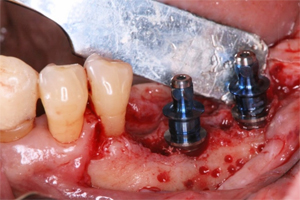

下顎左側臼歯部のインプラント治療

抜歯した下顎左側臼歯部にインプラント2本を埋入

骨再生

インプラント埋入と同時に骨増大を図り、インプラント周囲に十分な骨が得られるよう骨再生を図りました。